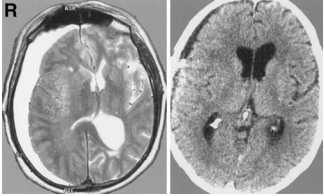

一位57歲的男子主訴突然頭痛和惡心。頭顱計(jì)算機(jī)斷層掃描(CT)顯示蛛網(wǎng)膜下腔出血(圖1)。他沒有進(jìn)一步的神經(jīng)癥狀,也沒有任何病史。血管造影顯示腦干右側(cè)有一個(gè)血管瘤病灶,由小腦上動(dòng)脈供血(圖2)。

圖1軸位電腦斷層掃描顯示基底節(jié)蛛網(wǎng)膜下腔出血

一次手術(shù)后三個(gè)月,病人在我科就診,主訴頭痛、步態(tài)共濟(jì)失調(diào)和左偏癱。磁共振成像顯示右半球硬膜下積液(圖5左)。進(jìn)行了兩次單獨(dú)的鉆孔手術(shù),后一次插入臨時(shí)硬膜下引流管,患者出院時(shí)無神經(jīng)功能缺損。

圖5左:軸位Tr加權(quán)磁共振成像顯示右半球硬膜下積液。右:硬膜下腹腔分流術(shù)插入后的軸向計(jì)算機(jī)斷層掃描。

兩個(gè)月后,病人再次入院時(shí)也有同樣的癥狀。CT顯示復(fù)發(fā)性硬膜下積液。插入硬膜下腹腔分流術(shù)。術(shù)后,病人表現(xiàn)良好,硬膜下積液在CT上完全消失(圖。5右)。在過去的2年里,他一直沒有因部分面部感覺遲鈍而抱怨。